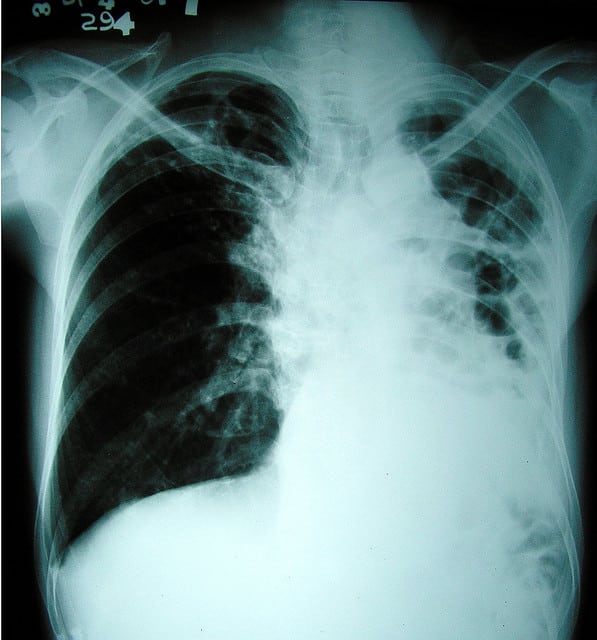

Les cas de tuberculose résistante aux traitements, souvent mortels, atteignent des niveaux alarmants dans certains pays, nécessitant des traitements de plus en plus complexes et coûteux, selon une nouvelle étude publiée jeudi par la revue médicale britannique Lancet.

Quelque 8,8 millions de personnes ont développé la tuberculose en 2010 et 1,4 millions en sont mortes, selon l’OMS qui estimait en 2010 que la tuberculose multirésistante touchait quelque 500.000 personnes chaque année, dont 150.000 décèdent.